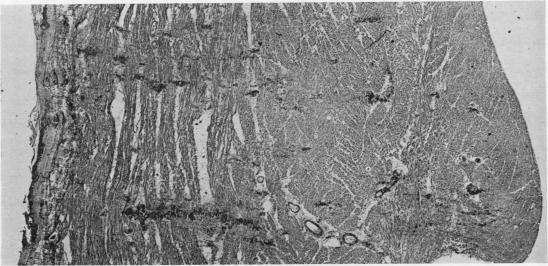

Primary amyloidosis: a review.

J Clin Pathol. 1956 Aug;9(3):187-211. doi: 10.1136/jcp.9.3.187.